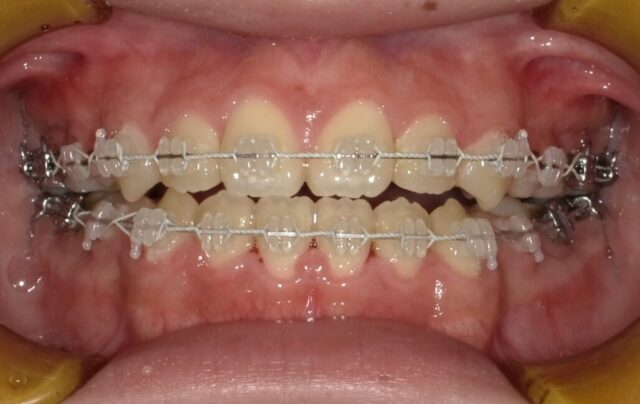

≪正面観≫

2023年5月

2025年1月